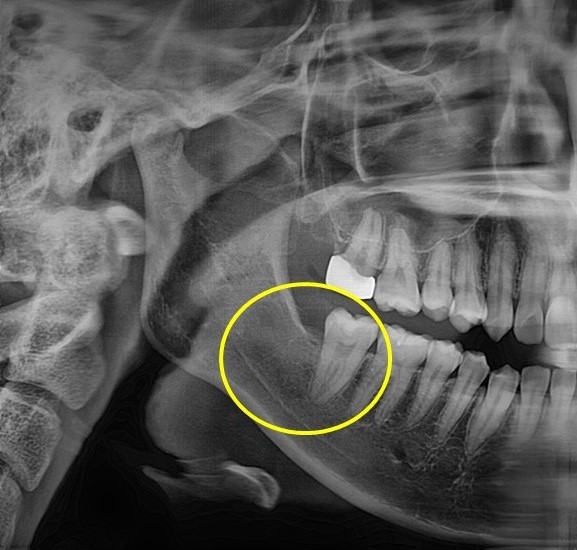

매복사랑니 발치사례

전후사진

수술 전

수술 후